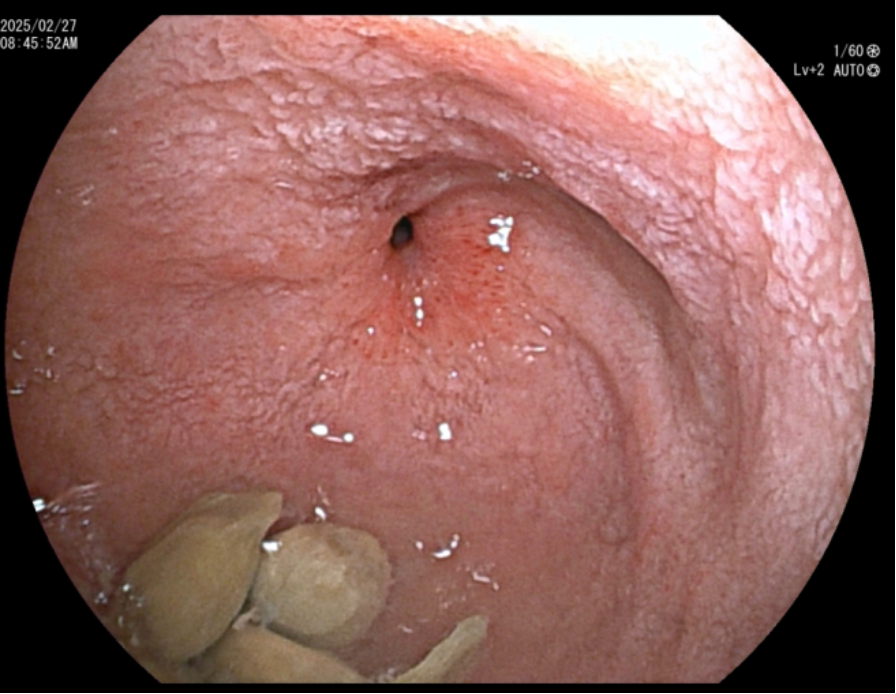

患者因呕吐1月,体重快速下降20斤,于外院行胃镜检查,发现十二指肠降段严重狭窄,狭窄处约3mm,这一狭窄有如路障,堵塞了进入消化道的食物。患者先进行保守治疗,无效后转诊至清华长庚。患者狭窄段周围解剖复杂,传统支架置入术难以实施。黄永辉教授团队决定采用目前国际前沿的EUS-GE技术,并针对手术难点实施创新性改进。

十二指肠降段狭窄处直径约3mm,葡萄籽都无法通过

经支架胃腔端实时造影显示支架通畅,远端肠腔显影(GIF动图)